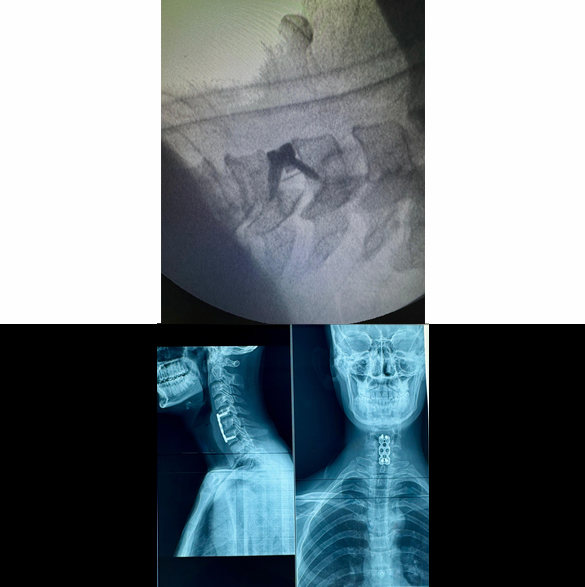

Cervical Disc Prolapse Surgery

Cervical disc prolapse surgery is performed to treat symptomatic cervical disc disease, by fusing the two segments as in traditional anterior cervical discectomy and fusion (ACDF) or by replacing the diseased disc with an artificial disc (also called cage). Sometimes, another procedure called anterior cervical corpectomy and fusion (ACCF) may be needed if two disc prolapse is present at two adjacent levels. Nowadays, cervical disc replacement surgery, also called Cervical Arthroplasty, is more frequently performed with better outcomes and even if disc prolapse is present at more than one level. Few complications of this surgery may be wound infection, bleeding, cerebrospinal fluid (CSF) leak, and nerve damage (rare and usually temporary).

Spinal Fracture Fixation/Fusion (Open and Minimal Invasive Surgery)

Spinal fractures generally require spinal instrumentation (fixation with screws and rods) in most cases, to main the spinal alignment and future complications like paralysis and kyphosis. These procedures usually require opening of the spine at back and placing screws and rods at multiple vertebrae. Early surgery is a key in the outcome of spinal fractures, because delaying the surgery patient may develop paralysis (weakness in power of limbs). New techniques like minimal invasive surgery (MIS) where large skin incision is not used, can also be performed in some patients. Complications of fixation/fusion surgery may include wound infection, bleeding, and implants/screws improper placement.